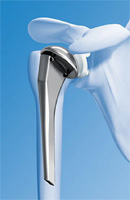

Dans un premier temps, on essaie le traitement médical associée à de la rééducation (il s’agit d’antalgiques et d’anti-inflammatoires non stéroïdiens). Quand ce traitement n’est plus efficace, on peut réaliser des infiltrations d’Altim. En cas d’échec des différents traitements, on envisagera une prothèse d’épaule. Une prothèse sert à remplacer la tête de l’humérus puisque le cartilage est usé. Elle peut également remplacer la glène de l’omoplate si celle-ci est usée. Plusieurs types de prothèses existent en fonction des causes de l’arthrose et le choix de la prothèse est fait avec le chirurgien.

Prothèse épaule |